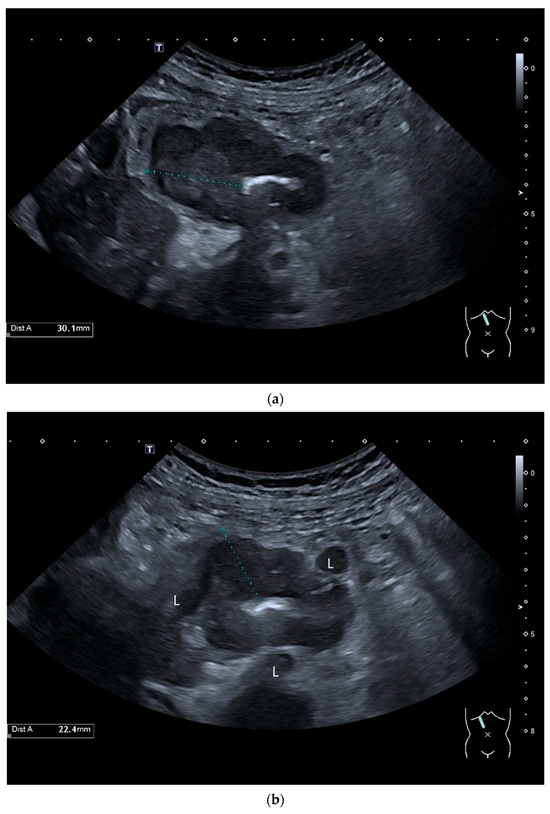

Figure 10.

Diffuse large B-cell lymphoma (DLBCL). In the right mid-lower abdomen, a large, smoothly circumscribed mass is present around the ileum (“pseudo kidney sign” (a)). Using a high-resolution linear transducer, the mass appears smoothly circumscribed and almost anechoic (b). The ileum runs centrally, and the echogenic wall is clearly defined (c). This wall does not merge into the mass. Since the mass is almost anechoic, it is also difficult in different transducer positions to distinguish whether it is a liquid lesion or a solid mass (b,c). CEUS with 2.4 mL SonoVue (9 MHz linear transducer) shows homogeneous arterial enhancement (d), but the intensity decreases with time in the venous phase (e). The ileal wall enhancement centrally within the mass is more intense than that of the tumor (d,e).